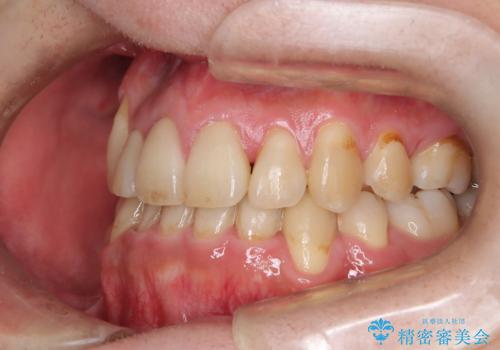

ガタガタの歯並び、八重歯をなおしたい、骨格性下顎前突 カモフラージュ矯正

- 前歯のガタガタと八重歯を治したいということで矯正を希望された患者様です。

骨格的に上顎骨が小さいために相対的に下顎骨が前に出ていたため、歯の傾きなど理想的な仕上がりが難しく、外科矯正ではなく歯列矯正の場合はカモフラージュ矯正になること説明の上、矯正治療を進めることになりました。

上顎は左右5番抜歯、下顎は左右4番抜歯しています。